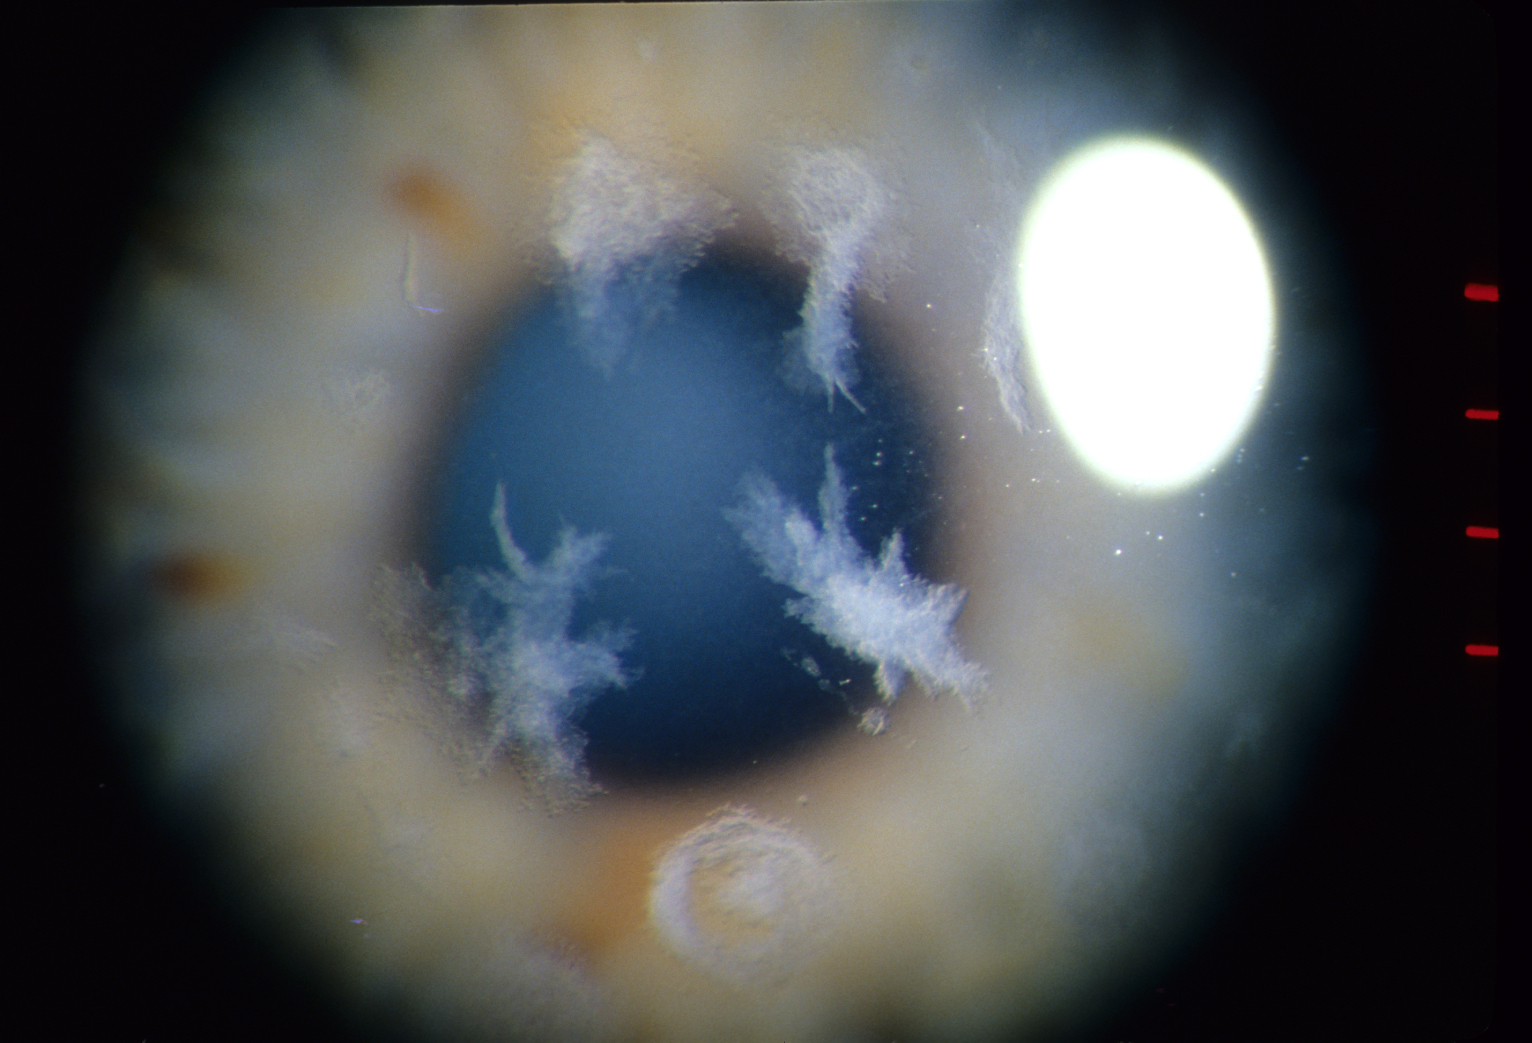

각막 검사에서 각막 중앙에 결정(crystal)이 반짝이는 듯한 모습으로 보이기에 이처럼 이름이 붙여졌습니다.

양측 각막의 중심부 상피하에 콜레스테롤 혹은 다른 지방 성분이 침착되는데,

이모양이 화환 모양의 둥근 형태로 침착되는 형태로 보입니다.

바늘모양의 다색선의 결절이 일정한 방향성 없이

주심부 각막의 보우만층 및 상부기질에서 관찰됩니다.